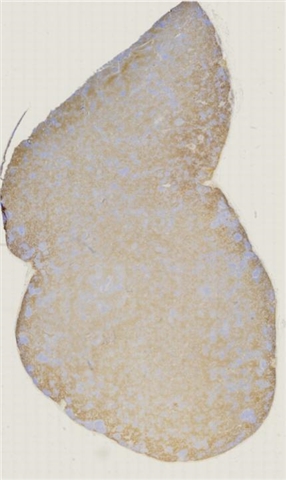

案例5 (6864)

性别:       年龄:62

患者详情: 发现双侧腹股沟肿物1月余。 查体: 双侧腹股沟可扪及多发肿大皮下肿物,大小约2*2cm,质中,边界尚清楚,活动度可,伴压痛,表面皮肤未见红肿破溃。 B超: 双侧腹股沟淋巴结肿大。 病理检查:腹股沟淋巴结穿刺活检提示淋巴组织增生。随行左侧腹股沟淋巴结切除术。

大体所见: 结节状肿物1枚,大小3×2×1.5cm,表面附有包膜,切面灰白灰红色,实性,质中。

医院: 上海长海医院